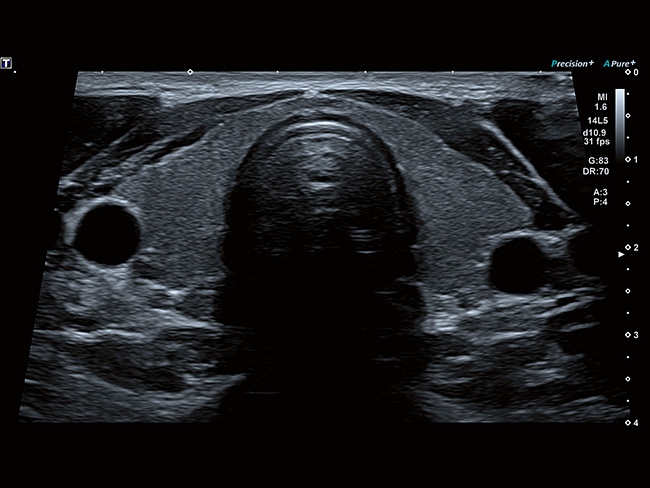

Стационарная цифровая ультразвуковая система Toshiba (Canon) a550. Современные технологии визуализации, цифровое формирование луча, удобная для работы панель. Характеристики, удовлетворяющие требованиям к системам УЗИ экспертного класса.

Система имеет компактные размеры, удобную центральную педаль блокировки, высококонтрастный экран в диагональю 23", регулировка по высоте на расстояние более 36 см, а панель управления и монитор могут быть настроены для любого положения сканирования.

Отличная цветопередача с высокой детализацией и четкостью изображения. Устройство подходит для профессионального использования в частных кабинетах и крупных медицинских центрах. Комплектация сканера применима для самых разных исследований. Широкий диапазон прикладного клинического программного обеспечения высокоэффективен для общих исследований, сердечно-сосудистых, гинекологических, ортопедических, урологических.